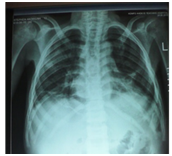

A 12-year-old boy was diagnosed with Sickle Cell Disease (SCD) with genotype SS about one year prior to. He presented with 2 months history of inability to walk and pain in both legs to Komfo Anokye Teaching Hospital in Kumasi, Ghana. The complaints were associated with marked weight loss and generalized body pain. He had been admitted about 2 weeks prior to the onset of current symptoms on account of abdominal pain and anaemia where he was haemo-transfused, given medications and subsequently discharged. There were no other significant findings in the past medical history, immunization history, nutritional and developmental histories. On examination he was found to be wasted (Weight for Height z-score <-3SD), pale, afebrile and anicteric. He had palpable axillary and inguinal lymph nodes (each measuring about 1cm to 1.5cm, mobile, non-tender and not matted). Vital signs were normal on admission. Other significant examination findings were obvious swelling of the right leg which was warm to touch, erythematous and tender on palpation. He had a gibbus deformity of the lower thoracic spine with no remarkable neurological findings in the lower limbs. A diagnosis of SCD with vaso-occlusive crises and cellulitis of the right leg was made with differential diagnosis of osteomyelitis, Deep Vein Thrombosis and Potts disease. Initial investigations revealed WBC of 13.51 X 109/dl with Neutrophils 8.83 (65.3%) Lymphocytes 4.27 (31.6%) and Monocytes 0.25(1.9%), Hemoglobin 7.1g/dl, MCV-70.7, MCH-22.4, Platelets: 538, ESR-117, INR-1.05, Prothrombin Time-14.3secs and blood sugar-6.5mmol/L. Malaria parasites were not seen on the blood smear and patient was negative for Retro-Viral Screen for HIV. Other investigations included Doppler Ultrasound, Chest X-ray, Pelvic x-ray, Thoraco-lumbo-sacral spine X-ray (Figure 1-10). Blood culture and sensitivity could not be done at the time of admission as microbiology service in the hospital had a brief logistic challenge. Radiological findings revealed the following: Reduction in the vertebral body heights of T7-T10 with associated reduction in the intervertebral disc spaces and crowding of the posterior ribs. A paravertebral soft tissue mass extending from T4 vertebral level to T11. Coarse trabeculation and sclerosis of the ribs noted. Expansion of the anterior end of the left 8th rib with ill-defined lytic areas. Buckling of the cortex of the lateral aspect of the left 9th rib, suggestive of a fracture. The imaged portion of the proximal humerus shows periarticular osteopenia. Also noted was relatively small left humeral head with left glenohumeral joint space. There are patchy homogenous opacities in both lung fields predominantly in the lower zones. There was associated silhouetting of the hemi diaphragms bilaterally and the cardiac shadow. There was generalized sclerosis of the imaged pelvic bones with coarsening of the trabeculae. The right femoral head was deformed and expanded with sclerosis and lytic areas within. There was associated narrowing of the right hip joint space. The left femoral head also showed patchy lucencies. No deformity of the left femoral head seen. The left hip joint space appeared normal. Also noted was fusion of the sacroiliac joints bilaterally. There was diffuse sclerosis of the imaged vertebrae with coarse trabeculae. The vertebral endplates of L1/L2 and L3/L4 showed sharp depression at the margins with a flat base centrally giving it the H shaped appearance. Also noted were ill-defined lytic areas in the L3 to L5 vertebrae with associated end plate irregularities and reduced intervertebral disc spaces at L3/L4 and L4/L5. No paravertebral soft tissue mass seen. No fracture or listhesis seen. Changes of the thoracic spine were described under the chest x-ray.

These radiological diagnostic features were suggestive of sickle cell disease with Thoracolumbar spondylodiscitis, likely pyogenic; Bilateral Avascular Necrosis of the femoral head (early on the left); Septic arthritis of the right hip and left shoulder joint; Osteomyelitis of the left 8th and 9th ribs. Doppler Ultrasound of the lower limb revealed the following: The right common femoral and superficial femoral veins were of normal lumen with good wall to wall compressibility, good colour doppler and spectral wave form properties. The right popliteal and posterior tibial veins however showed extensive echogenic intraluminal-filling defect with resultant loss of wall-to-wall compressibility (percentage stenosis 76%). The accompanying arteries were of normal size and caliber and showed good colour doppler and spectral properties. There was thickening of the subcutaneous tissue with dilated fluid channels seen in the right foot. Inguinal as well as popliteal lymph nodes with retention of their fatty hilum noted averaging 0.9*0.5cm. Also noted was a 1.4*0.9*1.5cm (volume about 1.0ml) anechoic collection with low-level internal echoes at the medial aspect of the proximal thigh muscles; suggestive of inflammatory changes. Based on the Doppler findings a clinical diagnosis of Right Popliteal and Posterior Tibial Vein Thrombosis with Pyomyositis in a Sickle Cell Disease patient was considered and patient was subsequently administered subcutaneous Enoxaparin 40mg daily as well as Warfarin 3mg nocte, IV Clindamycin 150mg qid, IV Ciprofloxacin. After 2 days of Warfarin and Enoxaparin, INR and PT were repeated and results were 1.1 and 15.1s respectively. The child was followed up closely for four weeks and subsequently discharge. A repeat Doppler finding revealed a completely resolved thrombus with no evidence of DVT.

Aseptic necrosis of the large bone heads is a common manifestation in the older SCD patients.25,26 The progression of aseptic necrosis is facilitated by malnutrition and secondary bacterial infections. This child presented with significant level of malnutrition (Weight for Height z-score <-3SD), osteopenia and evidence of joint space narrowing are clearly risk factors for progressive aseptic necrosis. Similar explanation above could account for the pathological rib fractures and the gibbus observed in this child. Acute Chest Syndrome (ACS) is one of the life threatening conditions of SCD and is usually confused with pneumonia in children.27,28 Clinicians should have high index of suspicion for ACS. This child did not present with ACS but radiological evidence of opacities in the lung field demonstrates past occurrence of ACS. DVT is not uncommon disease in children and cases have been reported.29,30 The occurrence of this disease is associated with risk factors such as cancers, trauma, infections, venous catheterization, sickle cell disease and coagulation disorders.29 This patient had two risk factors for DVT; Sickle Cell Disease and possible multiple infections.31 In addition to these risk factors, was the fact that this child was immobile for most of the time during the onset of the illness (suffering from septic arthritis of the hip and pyomyositis). In SCD patients, presentation with lower limb pain and tenderness is mostly associated with vaso-occlusive episodes and/or osteomyelitis in areas with high prevalence of the disease. Clinicians should have a high index of suspicion for DVT since it can occur in cases with multiple risk factors. This is critical since the occurrence of Pulmonary Embolism (PE) from the DVT will be life threatening and could also be easily confused to be ACS in a SCD patient and patient would be mismanaged. This short case report therefore tried to highlight some of the uncommon pathologies amongst others that might arise in a SCD patient and to alert clinicians to look out for DVT as an uncommon differential diagnosis in swollen limbs in these patients. It is worth noting that attention needs to be paid to a multi-disciplinary preparedness and response approach to the management of SCD patients, as presented in this case report, to mitigate or minimize disability and mortality.